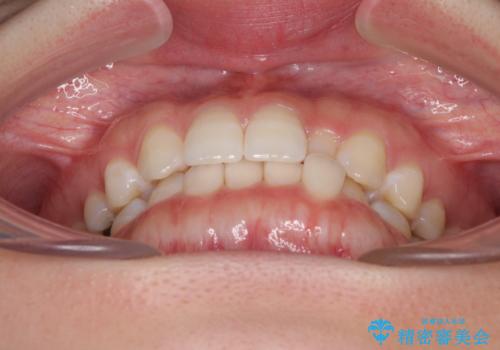

海外転居前に気になる前歯を整えたい 上下前歯の部分矯正

- 1年後に海外に転居するため、気になる前歯を矯正治療で整えたいとのことで来院された患者様です。

下顎は叢生が強かったため、奥歯までワイヤーを装着し、上顎は前歯の一部のみ気になっていたので、その部分にだけワイヤー装置を装着することとしました。